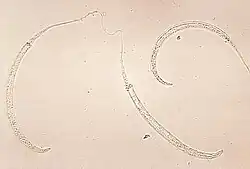

Riszta, nitkowiec podskórny, robak medyński (Dracunculus medinensis) – pasożyt podskórny człowieka, a także małp, psów, koni, bydła i innych ssaków. Wywołuje chorobę zwaną drakunkulozą. Obecnie występuje tylko w tropikalnych rejonach Afryki.

Samica osiąga długość do 120 cm, samiec do 4 cm. Samice są jajożyworodne. Zarazić można się poprzez wypicie wody, w której znajdują się oczliki zarażone larwami nicienia. W przewodzie pokarmowym żywiciela ostatecznego larwy uwolnione z oczlików dojrzewają i kopulują, a zapłodnione samice wędrują miesiącami w organizmie żywiciela. Umiejscawiają się w tkance podskórnej, najczęściej kończyn dolnych. Oddychają powietrzem atmosferycznym poprzez otwór wywiercony w skórze. W miejscu lokalizacji pasożyta tworzy się pęcherz wrzodowy. Przy zetknięciu z wodą pęcherz pęka i przez powstałą szczelinę częściowo wysuwa się samica. Przez pęknięty wór powłokowo mięśniowy samica wysuwa macicę, która również pęka na skutek czego larwy przedostają się do wody. Uwolnione larwy wnikają do oczlików, dwukrotnie linieją i po około 2 tygodniach osiągają dojrzałość inwazyjną. U człowieka nieusunięcie pasożyta prowadzi do zapalenia naczyń chłonnych i żył oraz do powstania miejscowych zgorzeli.